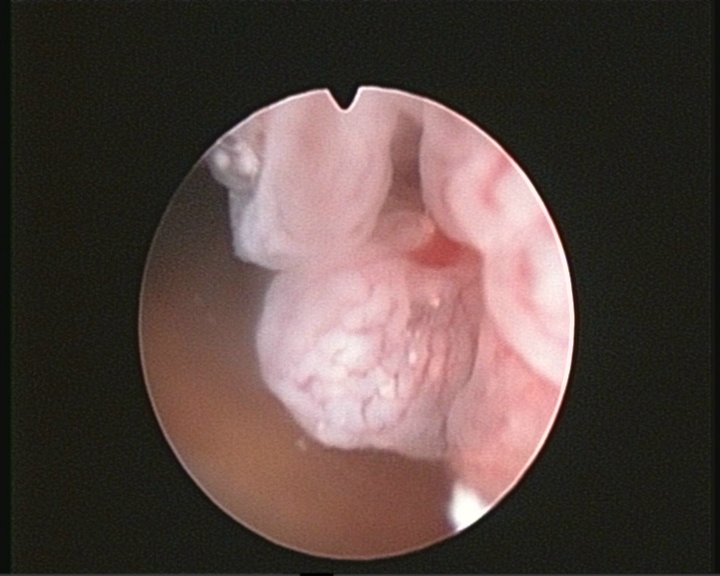

Endometrial cancer is the most common gynecological cancer in developed countries and is the 5th most frequent cancer affecting woman. The estimated frequency is 19.1 / 100,000 cases in the USA and Canada and 15.6 / 100,000 in Europe.

It is usually associated with menopause, although up to 14% of cases are diagnosed in premenopausal women and up to 5% of cases in patients under the age of 40 years. It is usually diagnosed in early stages and with the tumor usually confined to the uterine cavity, which generally gives it a good prognosis